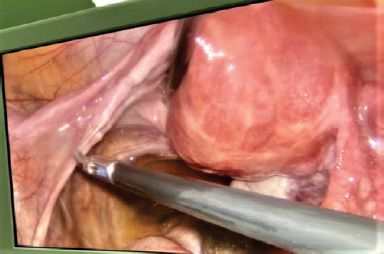

В позадиматочном пространстве располагается образование малого таза (образование напоминает яичник 30 × 30 × 25 мм с маточной трубой с признаками «старого» некроза и кальцинированной перекрученной ножкой кисты (рис. 2).

Рис. 2. Образование малого таза в позадиматочном пространстве / Fig. 2. Pelvic lesion in posterior cul-de-sac